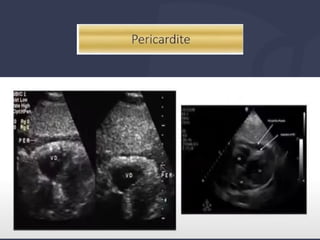

● Este paciente tem SCA, IC, TEP, Tamponamento,

Dissecção???

SIM, NÃO e INCONCLUSIVO